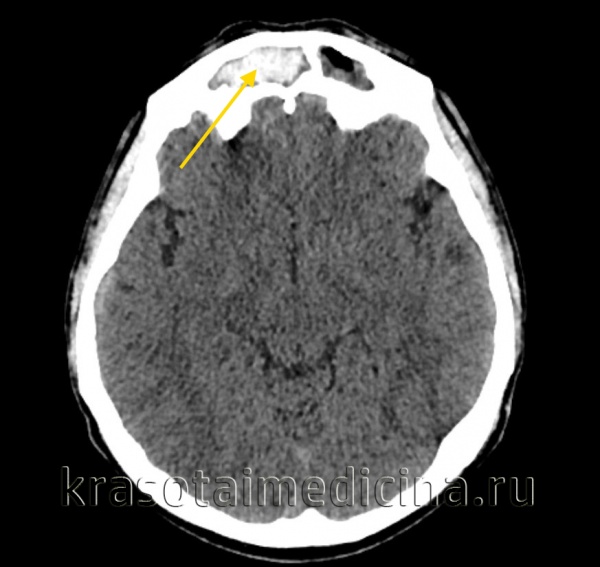

КТ ППН. Этот же пациент. Диффузное снижение пневматизации обеих лобных пазух, справа с гиперденсными включениями (желтая стрелка).